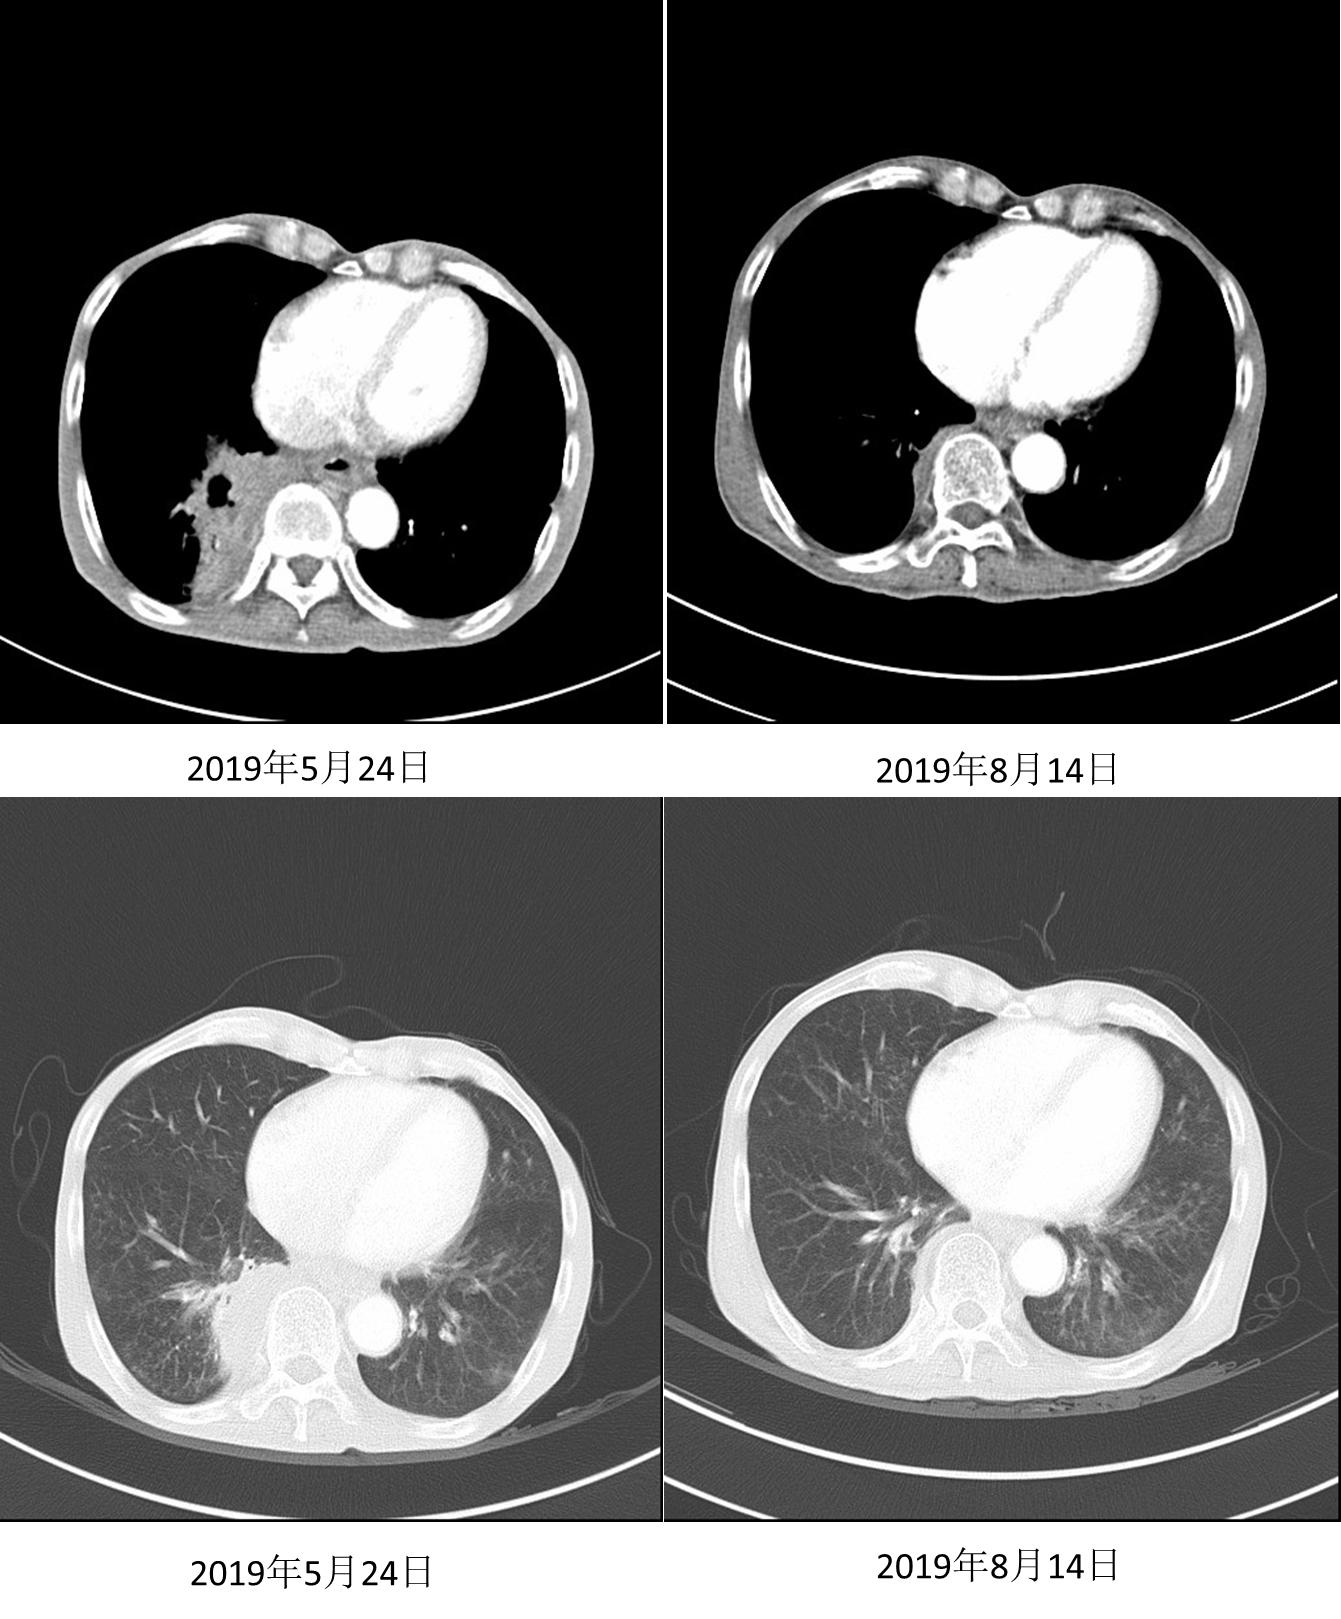

三线治疗

在沟通疗效和价格等因素后,患者自行选择信迪利单抗。2019年4月3日、4月30日、5月21日行信迪利单抗200mg D1治疗3个周期,患者症状缓解(自诉从“躺在床上”到“早上逛菜市场”)。2019年5月24日复查胸部CT示:右肺下叶软组织肿块影范围较前明显缩小,强化不均,范围约77mm *50mm。

图4. 2019年5月24日复查

2019年6月12日、7月2日继续行信迪利单抗200mg D1治疗2周期。2019年8月14日继续随访CT,结果示右肺下叶软组织肿块影范围较前明显缩小,强化不均,范围约28mm * 20mm,邻近胸膜增厚。疗效评价为部分缓解(PR),接近完全缓解(CR)。

图5. 2019年8月24日复查